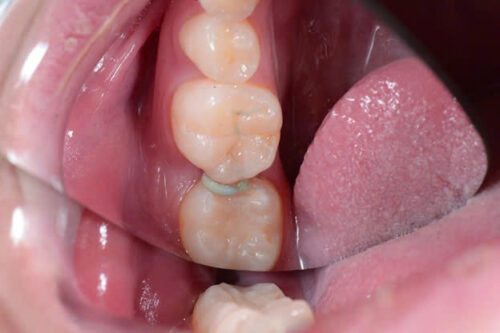

Quy trình lâm sàng phục hồi đường hầm

Bước 1: Đặt chun tách khe

Bước 2: Tháo chun, làm sạch và tạo xoang trám bằng kỹ thuật đường hầm

Bước 3: Trám phục hồi